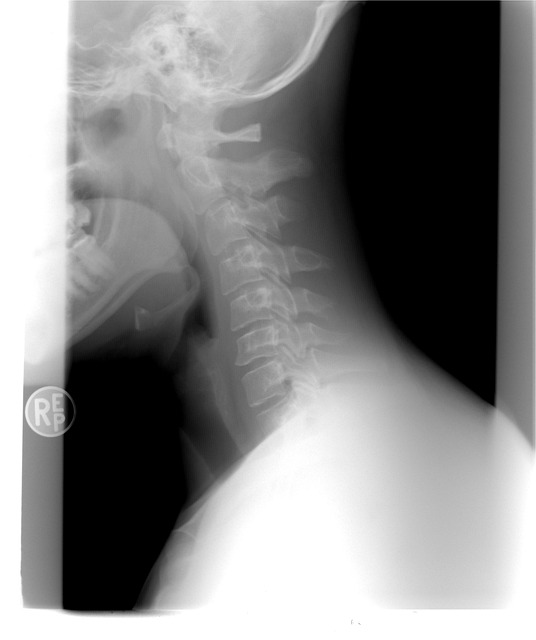

거북목 증후군은 고개를 앞으로 내밀어 목의 C자 형태의 자연스러운 곡선이 사라지고 일자로 펴지면서 통증을 유발하는 증상입니다. 장시간 컴퓨터 사용이나 스마트폰을 고개를 숙인 상태로 사용하는 것이 주요 원인으로 작용합니다.